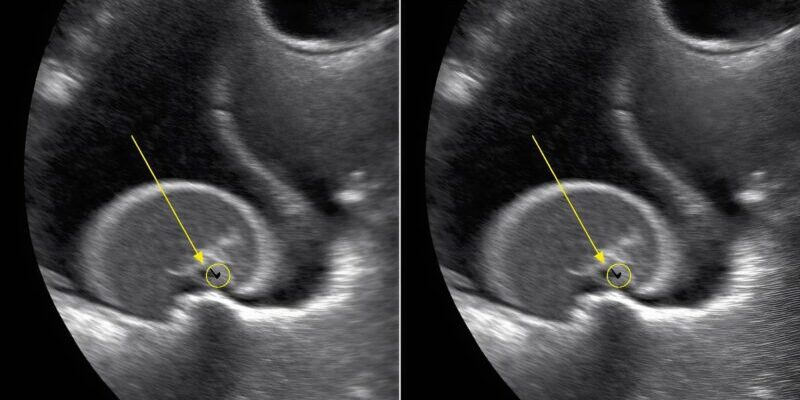

The ultrasound showed that Lily had accidentally swallowed several small magnetic pieces from a toy. Inside her intestines, the magnets had attached to one another through the intestinal walls, creating a dangerous obstruction. The doctor explained that these tiny objects, when swallowed separately, can attract each other inside the body, causing severe internal complications.